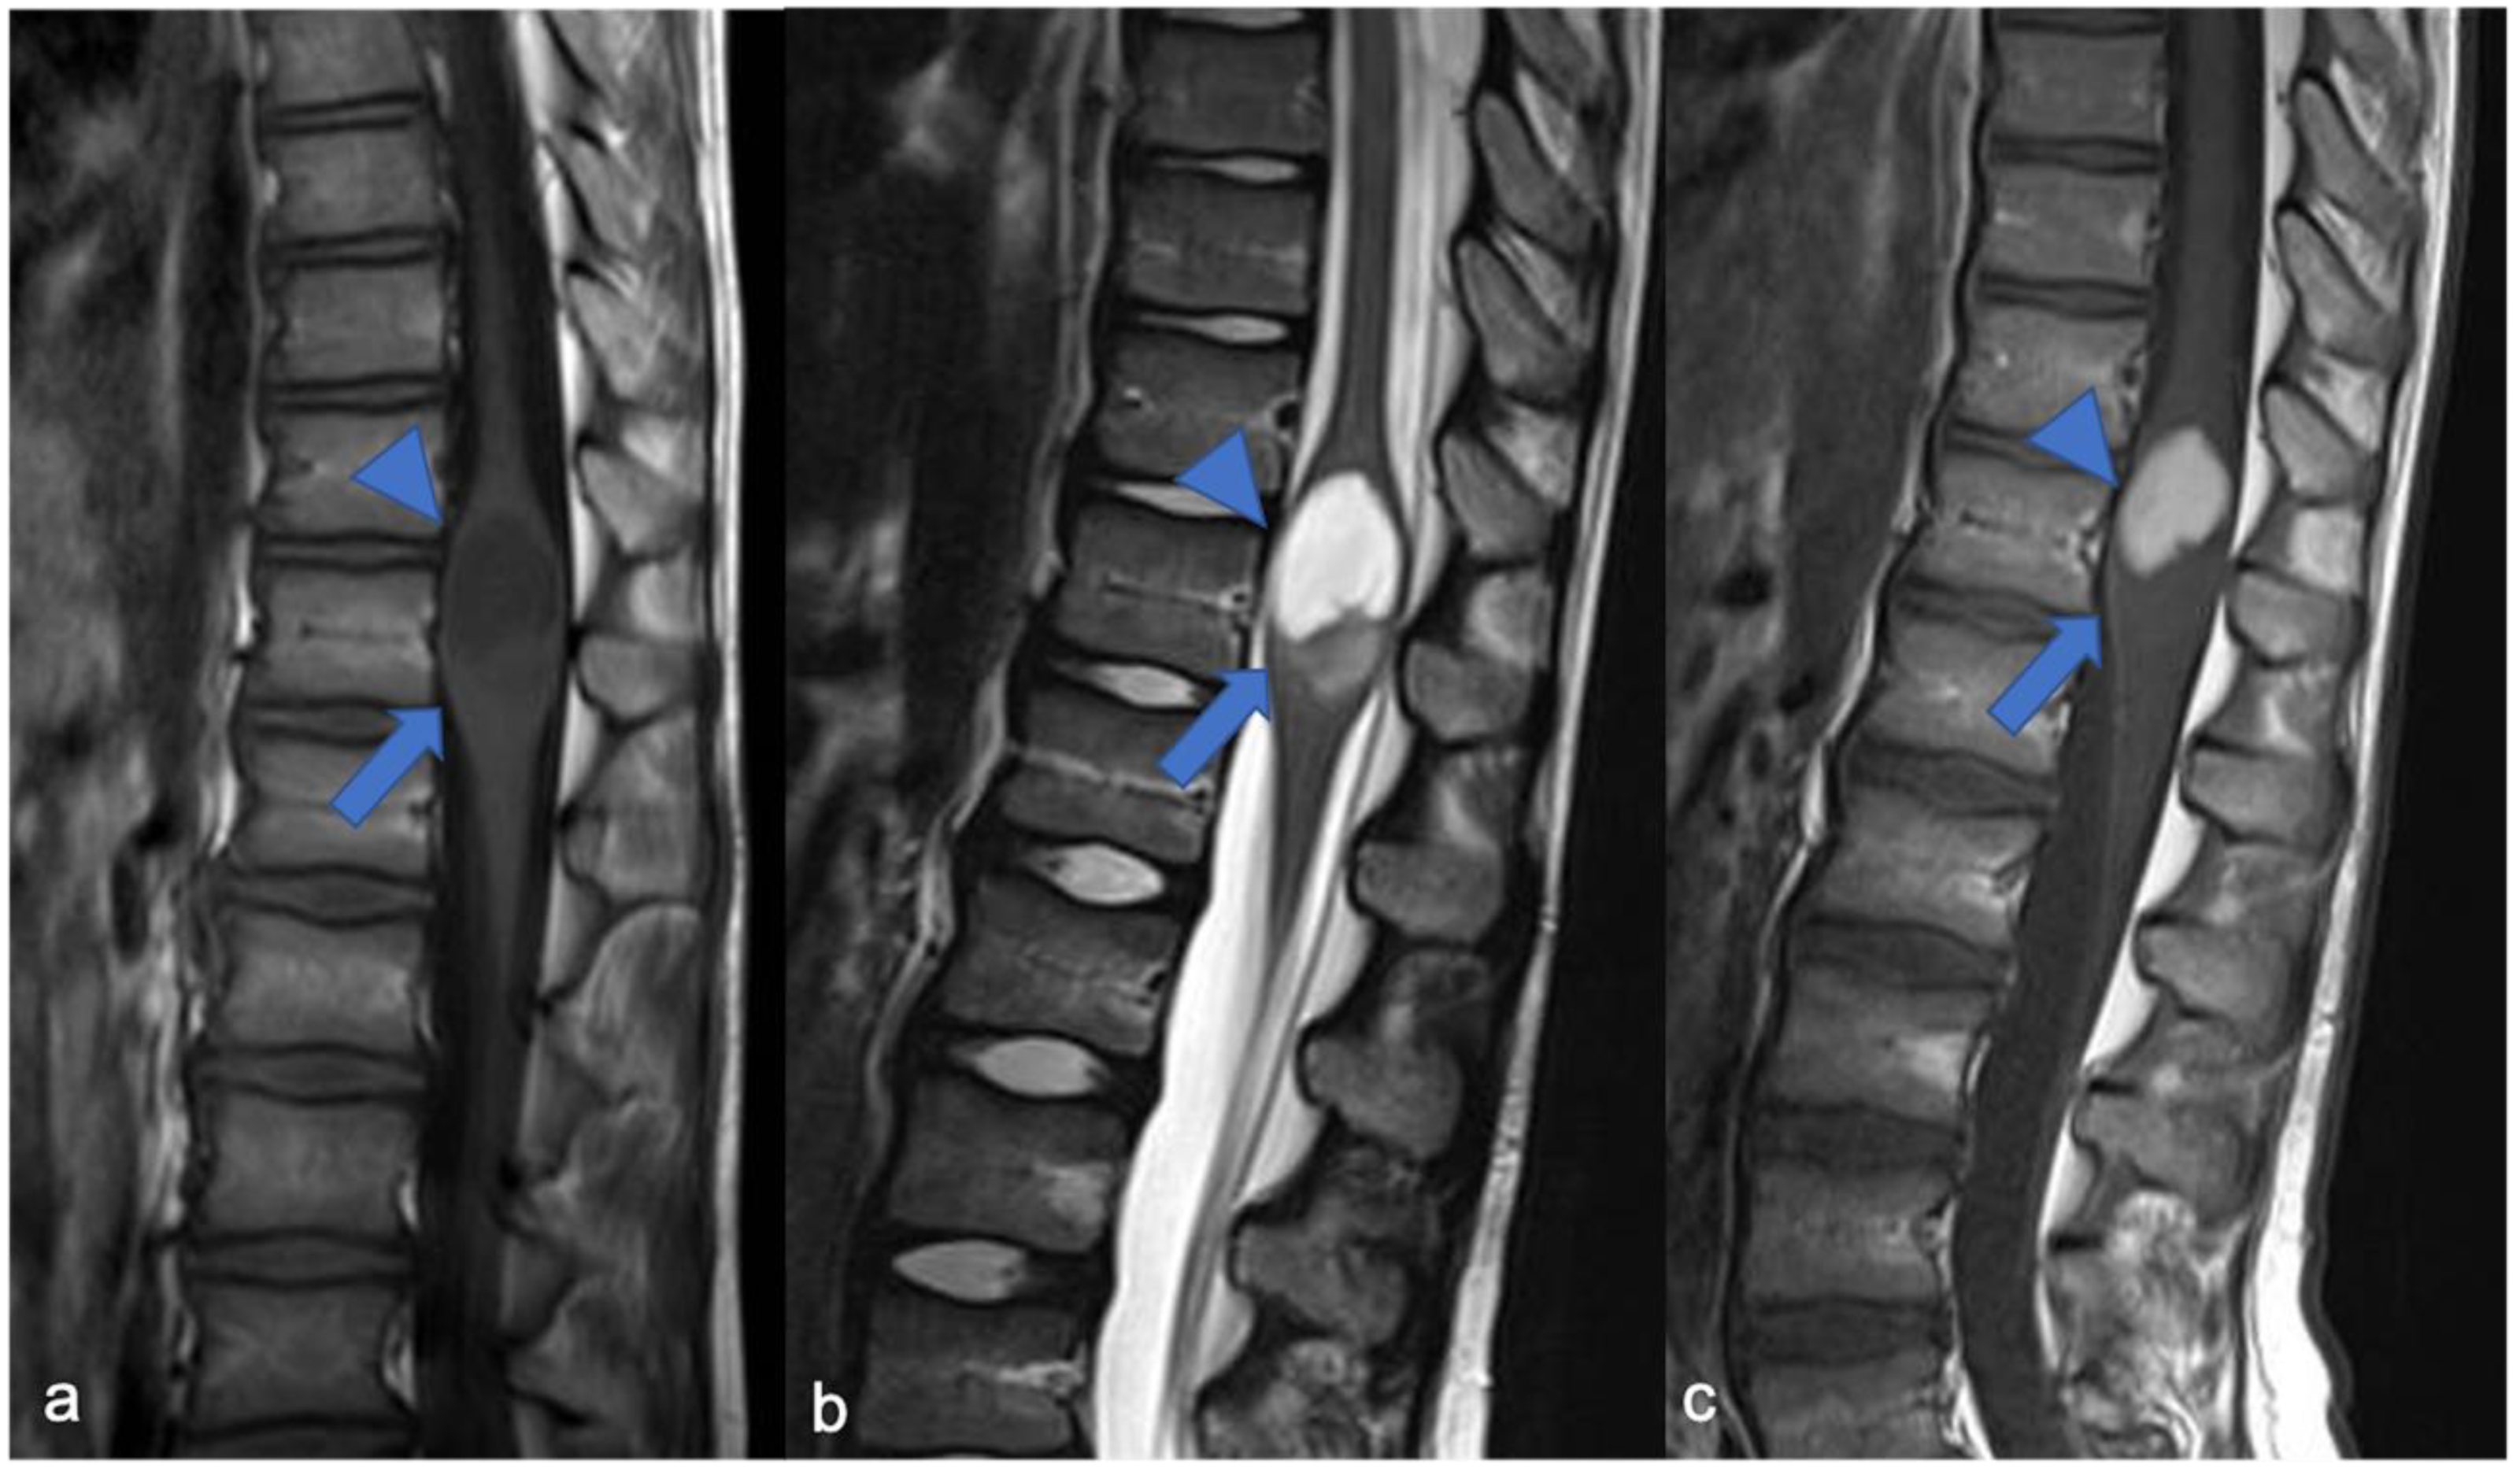

2. Gliomas and Mixed Neuronal–Glial Tumors

2.1. Gliomas